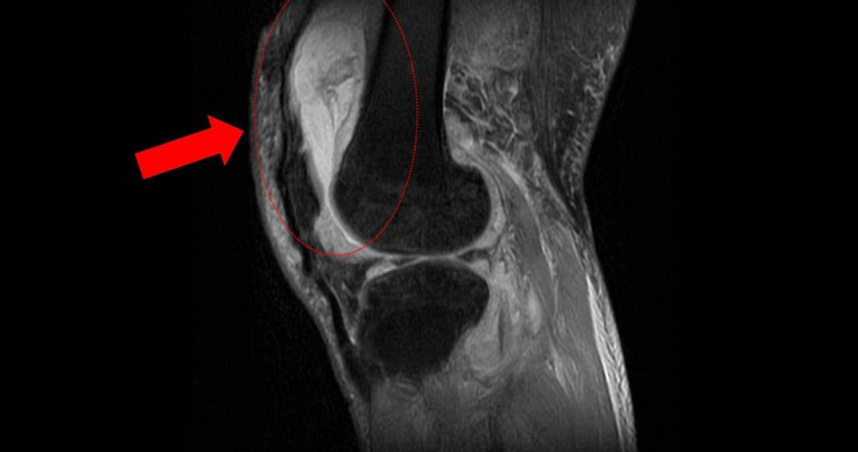

膝關節疼痛竟是結核菌引起。(圖/台中慈濟醫院提供)

據了解,賴先生長期左膝腫痛、幾乎無法行走,剛開始以為只是退化性關節炎,服用止痛藥、抽關節積水、熱敷復健數月卻越來越嚴重,就醫時膝蓋已腫脹無法彎曲。周立展抽取膝關節液化驗後發現,白血球數值雖偏高,但並非典型的細菌感染,懷疑有其他原因,於是安排病人住院,進一步透過X光與磁振造影檢查,顯示膝蓋內已有大量積液並化膿,屬於嚴重關節感染。